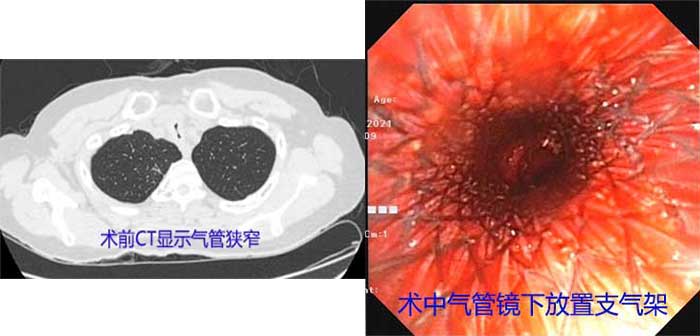

11月患者出现咳嗽、气喘,伴有严重喘憋、呼吸困难。入院后,经CT检查发现患者最狭窄的地方是组织气管的上段,直径仅为正常成人的1/4,整个肺部通气功能受到限制,不及时处理容易造成严重的呼吸衰竭和肺部感染。时间就是生命,黄德良主任带领医疗团队,紧急制定手术方案,争分夺秒进行气管支架置入术,置入支架来支撑气道、扩张狭窄段。凭着娴熟的技术,克服了技术难度高,风险大的问题,目前患者病情得到平稳控制,转入病房作进一步治疗。